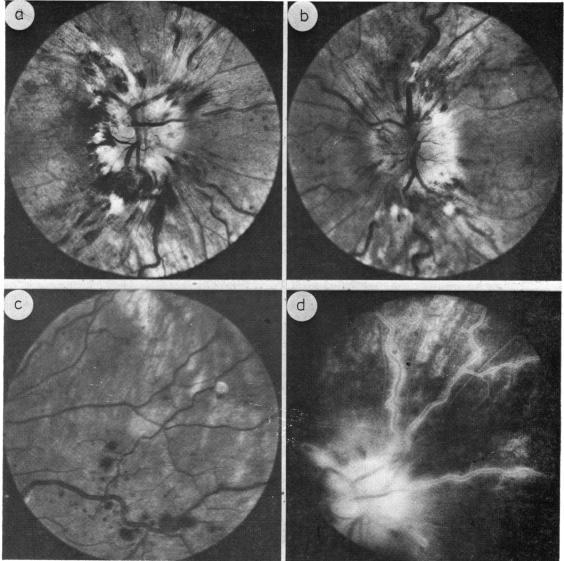

Peripheral retinal haemorrhages with papilloedema.

Two cases are described with severe intracranial hypertension, papilloedema, and a hitherto unreported haemorrhagic peripheral retinopathy. The marked disc swelling in these patients has probably contributed to a venous occlusive element resulting in the haemorrhagic retinopathy.